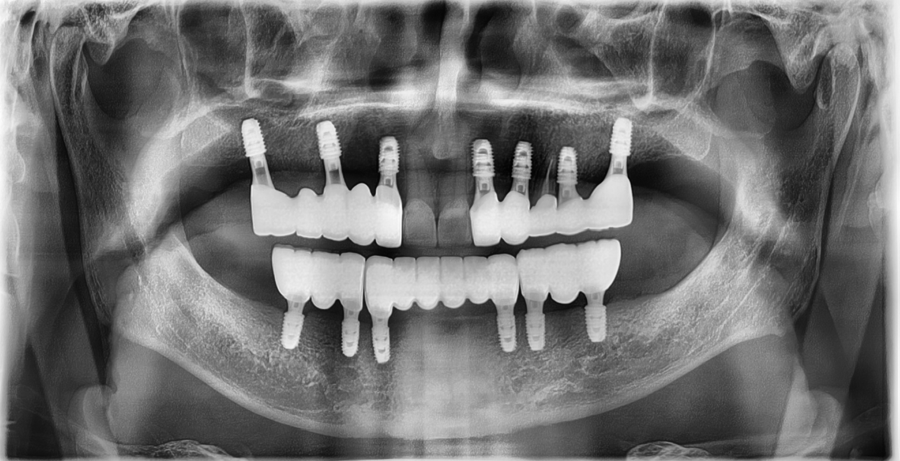

정밀 진단

저희 잠실 치과 서울오브치과병원에서는

시니어 환자분들도

3D 스캐너·구강내시경·교합 검사를 통해

현재 치아 상태를 세밀하게 확인하고 있습니다.

검사 결과,

앞니는 치질이 충분히 남아 있어

과도한 삭제 없이도 라미네이트가 가능했고,

잇몸 상태도 안정적으로 유지되고 있었습니다.

교합 또한 큰 문제 없이 맞물리고 있어

기존 보철물의 색과 형태만 개선해도

더 자연스럽고 균형 잡힌 앞니 라인으로

회복될 수 있는 케이스였습니다.